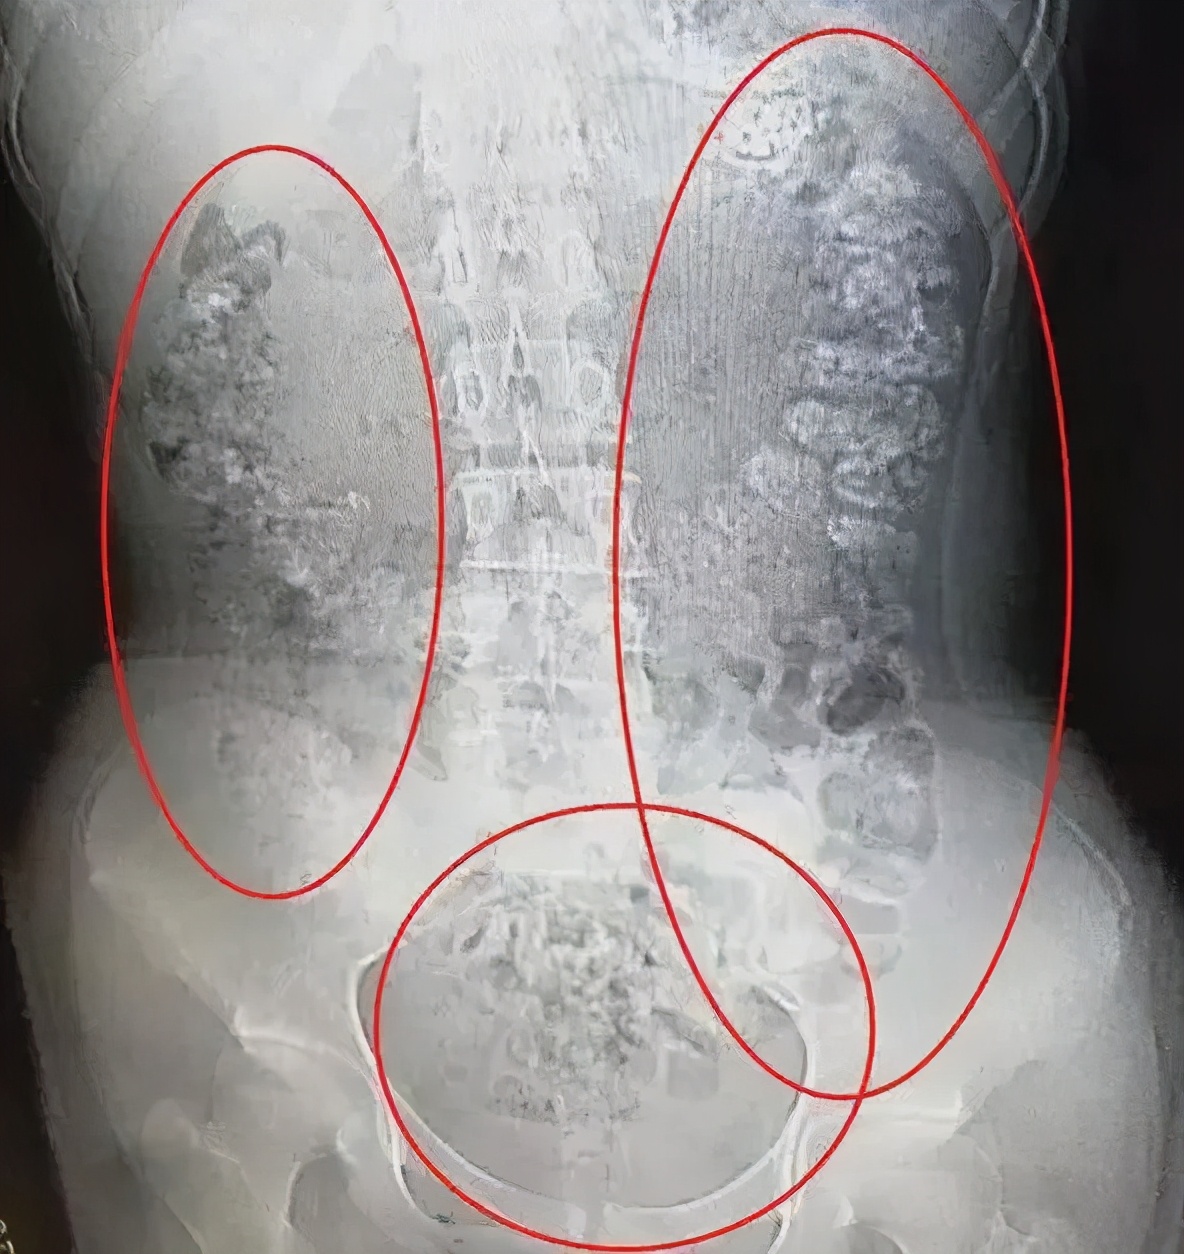

来自浙江的14岁女孩小沈(化名),因肚子疼,有好几天无法排便,也吃不下东西,来到医院做了腹部的CT。本来以为是普通的肠胃病,可没想到检查结果,让医生一惊:

患者胃部、横结肠、升结肠

降结肠、乙状结肠

一直到肛门

全都是 颗粒状阴影

足足有百余颗之多

这么多颗粒状阴影究竟是什么东西呢?在医生的问询下,患者小沈才道出了实情。原来小沈5天前喝了一杯珍珠奶茶,而喝下去的珍珠,没有被消化掉,堆积在小沈的肠胃处。